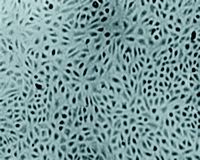

首先,我们选择CAM模型初步评价麝香保心丸的促血管生成活性。鸡胚用孵育第7天的香港麻花鸡白皮种蛋,微孔滤膜作为载体,加入麝香保心丸药液,阳性和阴性对照分别用重组碱性成纤维细胞生长因子(bFGF)(贝复剂)和生理盐水,3天后固定CAM标本,计数一级、二级血管来评价促血管生成活性。结果显示,保心丸组CAM两级血管数均比阴性对照组明显增加(保心丸组的一、二级血管数分别为35和50,阴性对照组则为21和33。n=12,P<0.05),初步表明麝香保心丸具有促血管生成活性(见图1)。

图1 麝香保心丸对CAM血管生成的影响

A:加有生理盐水的CAM

B:加有麝香保心丸的CAM